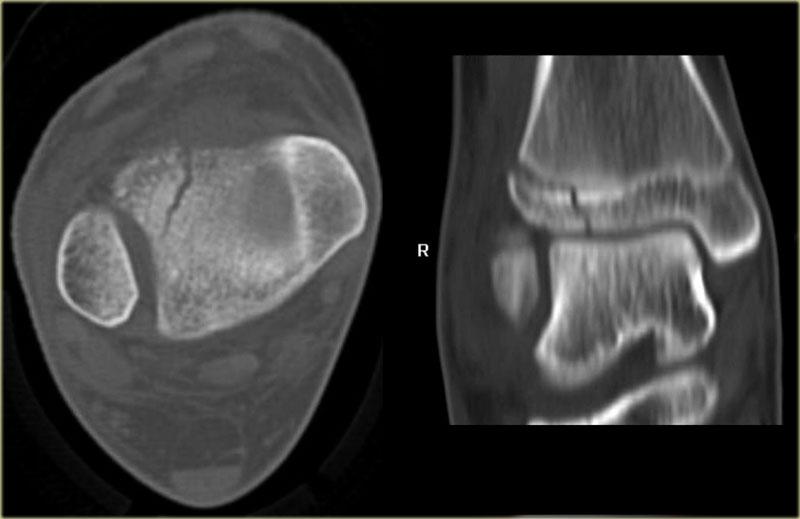

Hãy quan sát các hình ảnh và sau đó cuộn sang hình ảnh tiếp theo.

Đường gãy qua đầu xương có thể dễ bị bỏ sót (mũi tên xanh).

Đường gãy qua tấm sụn tiếp hợp chỉ được phát hiện trên CT.

Tiếp tục xem các hình ảnh CT.

Các hình ảnh CT thể hiện rõ ràng đường gãy qua tấm sụn tiếp hợp và đầu xương.

Đây cũng là gãy xương Salter-Harris type III.

Lưu ý rằng đồng thời có gãy xương Tillaux.

Chúng ta sẽ thảo luận về các gãy xương này ở phần tiếp theo.